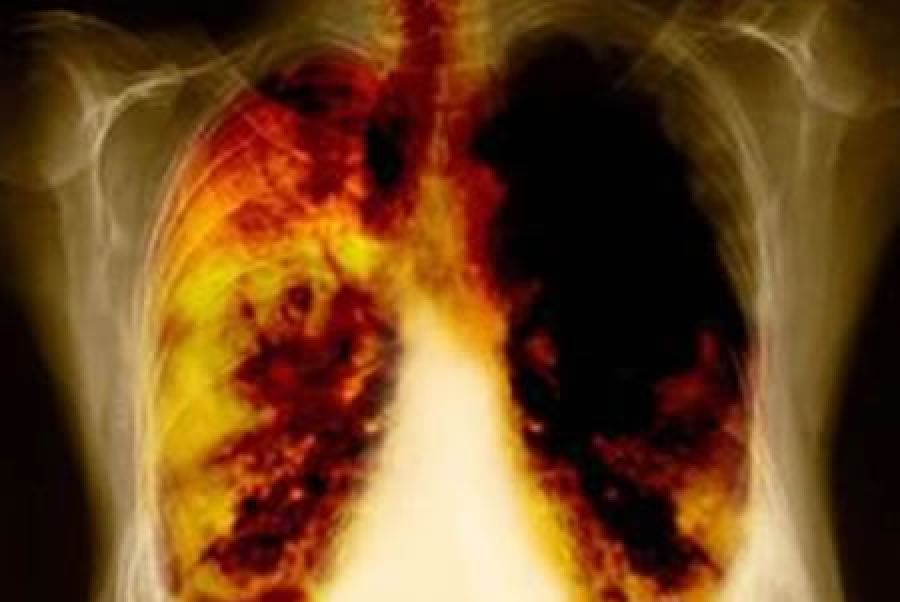

Para contribuir en la reducción del índice de mortalidad se han realizado diversas investigaciones enfocadas en incrementar el nivel de supervivencia de los pacientes. Es el caso, por ejemplo, del desarrollo de tratamientos de primera línea, como osimertinib, cuya característica principal es ayudar a inhibir tanto las mutaciones sensibilizantes el EGFR (factor de crecimiento epidérmico) como de aquellas que presentan resistencia y, por consecuencia a reducir a más de la mitad el riesgo de progresión. Logrando de esta manera que los pacientes incrementen su esperanza de vida de 1 año y medio a 3.

En el caso de pacientes diagnosticados con cáncer de pulmón en Fase III (antes de llegar a la etapa IV, donde el cáncer se ha extendido a otros órganos), ya también es posible incrementar su esperanza de vida a través de una nueva inmunoterapia, durvalumab, como tratamiento posterior a la quimio-radioterapia en pacientes que no pueden ser operados, la cual mejorar la supervivencia en comparación con el tratamiento estándar y reduce el riesgo de muerte en un 32%.

“Lo importante es comprender que la tasa de mortalidad por cáncer de pulmón y otros tipos de cáncer se puede disminuir significativamente si los casos se detectan a tiempo y reciben un tratamiento eficaz. Es necesario cambiar las prácticas clínicas y acercar a los pacientes a tratamientos innovadores pues los beneficios son evidentes: mayor probabilidad de supervivencia, menor índice de morbilidad y un menor costo en el tratamiento si es enfocado a cada estadio de la enfermedad”, indicó José Francisco Corona oncólogo del INCan durante la ponencia sobre cáncer de pulmón en etapa III en el Congreso Oncológico en Cancún.